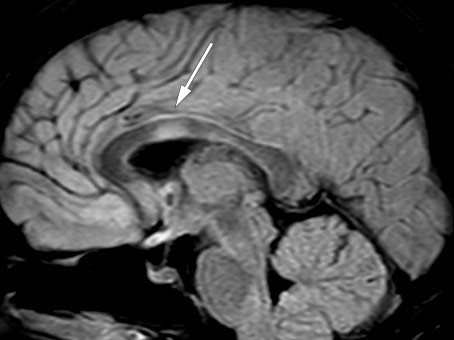

After discharge, the second serum anti-MOG test was found to be positive. Towards the end of the prednisolone taper, the patient had two brief admissions to the medical department owing to persistent headache and urinary tract infection. MRI of the brain and spinal cord and neurological examinations revealed no new findings at this point. Immediately after discontinuation of prednisolone, the patient was admitted to the neurology department with increasing visual impairment, diplopia, right-beating nystagmus, and abduction paresis in the right eye. An MRI 20 days after the previous examination and almost two months after rituximab initiation, revealed new bilateral frontal subcortical lesions as well as in the medulla, left cerebellar peduncle and corpus callosum (Figure 4). Lumbar puncture still showed moderate pleocytosis (Table 1, last column). As before, the patient received methylprednisolone with good effect, and was then discharged home with long-term prednisolone tapering and prompt follow-up at the outpatient clinic.

Figure 4 Lesion in the corpus callosum on sagittal FLAIR-MRI.

A third test confirmed positive anti-MOG status. The patient's overall medical history, including exacerbations shortly after discontinuation of prednisolone, was also consistent with anti-MOG encephalomyelitis (7). Lesions in the corpus callosum are common in multiple sclerosis, but may also occur in cases of adult anti-MOG encephalomyelitis (8).